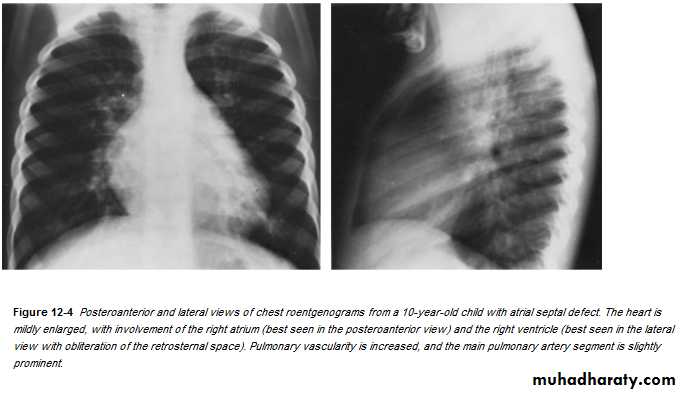

ATRIAL SEPTAL DEFECT (CONT.):

• Dx:• CXR:

• 1. Cardiomegaly of RV configuration. 2. Round apex peak.

• 3. Increase pulmonary marking

•